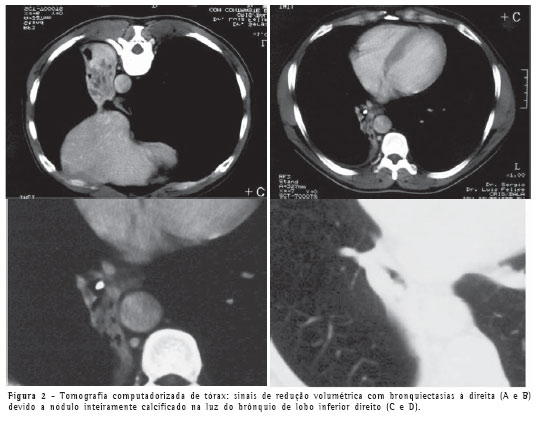

A tomografia computadorizada de tórax confirmou a atelectasia e mostrou pequena lesão calcificada em luz de brônquio no lobo inferior direito (Figura 2), além de bronquiectasias com provável impactação mucóide no lobo pulmonar colapsado.